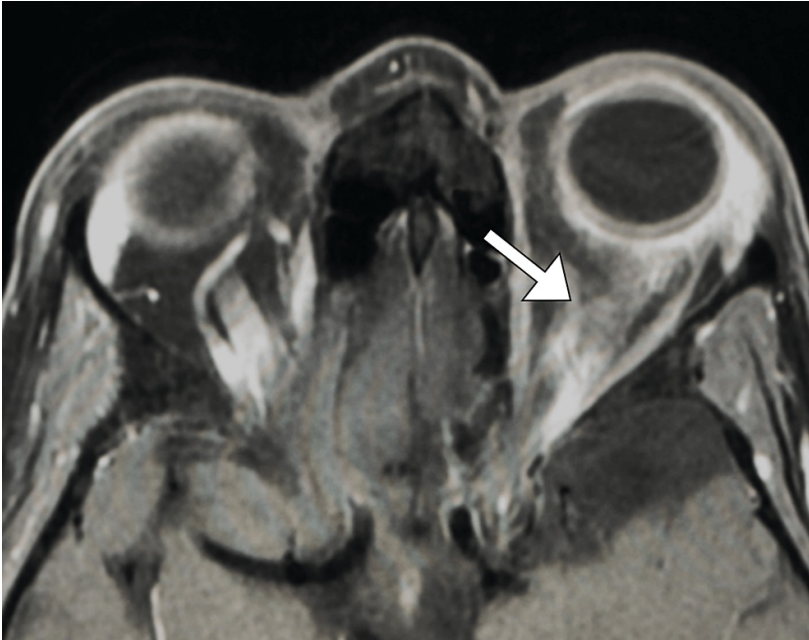

病史摘要:83 岁老年男性,因“前额疼痛性红斑性皮损持续一周”至急诊科就诊,初诊丹毒,口服克林霉素。一天后疼痛加剧,前额及左眼周围出现水疱性皮损,转诊眼科。患者曾因青光眼使用降眼压滴眼液。诊疗过程:眼部检查未见玻璃体或视网膜血管炎,Hutchinson 征阴性。诊断为眼带状疱疹(HZO),给予口服伐昔洛韦。次日出现复视,检查发现左眼内收等受限伴眼睑下垂。眼眶 MRI、脑 MRA 及